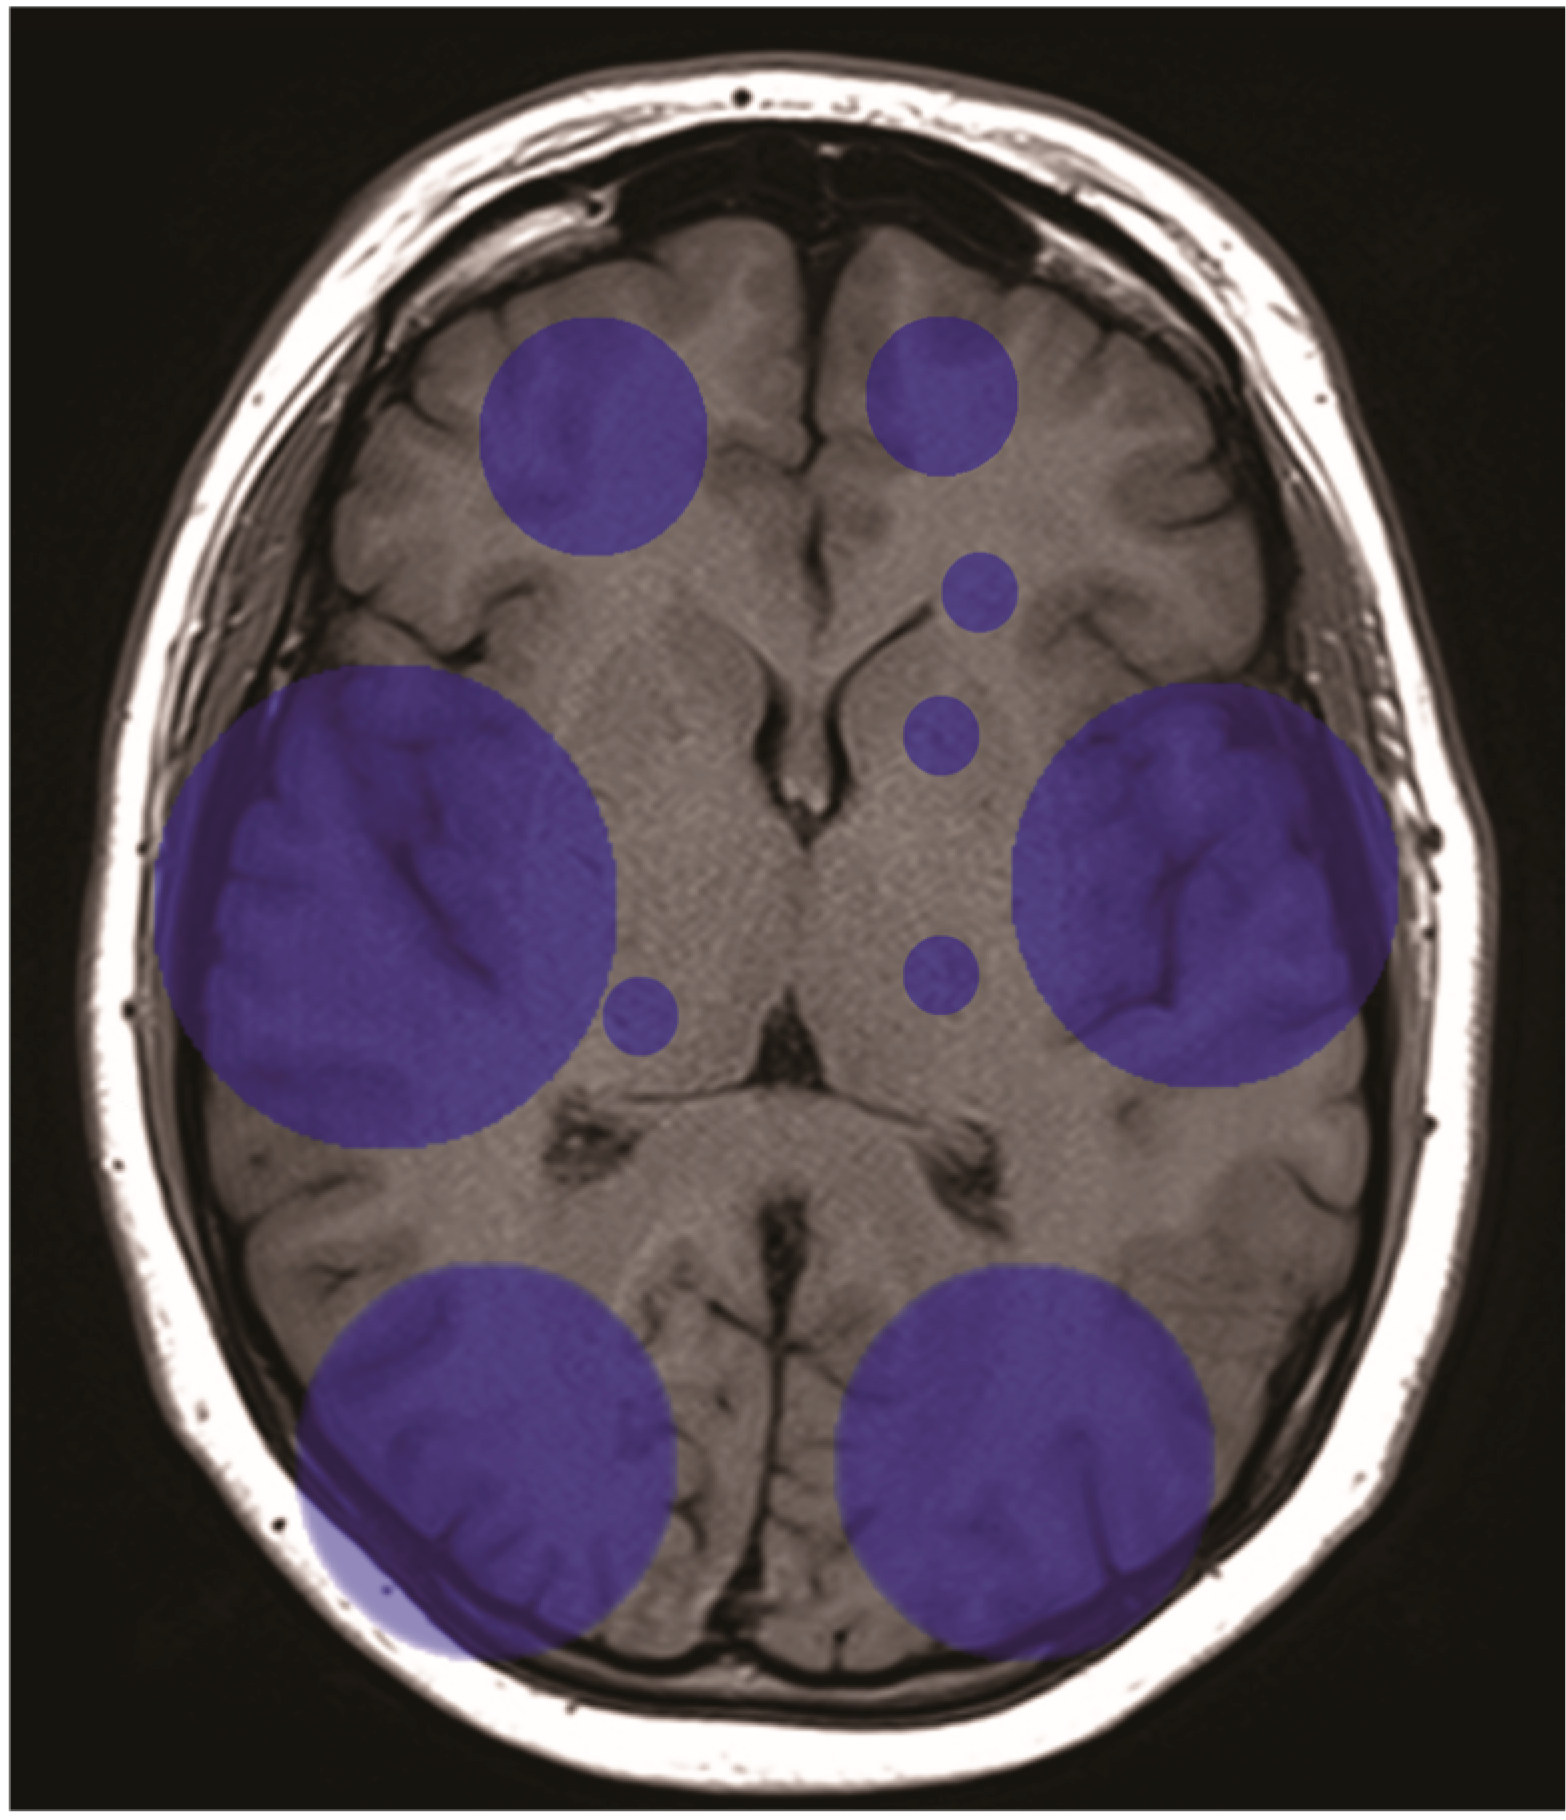

3.3.2. Postoperative Stroke Data Analysis